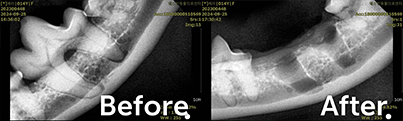

강아지의 발치전후 엑스레이

고양이의 발치전후 엑스레이